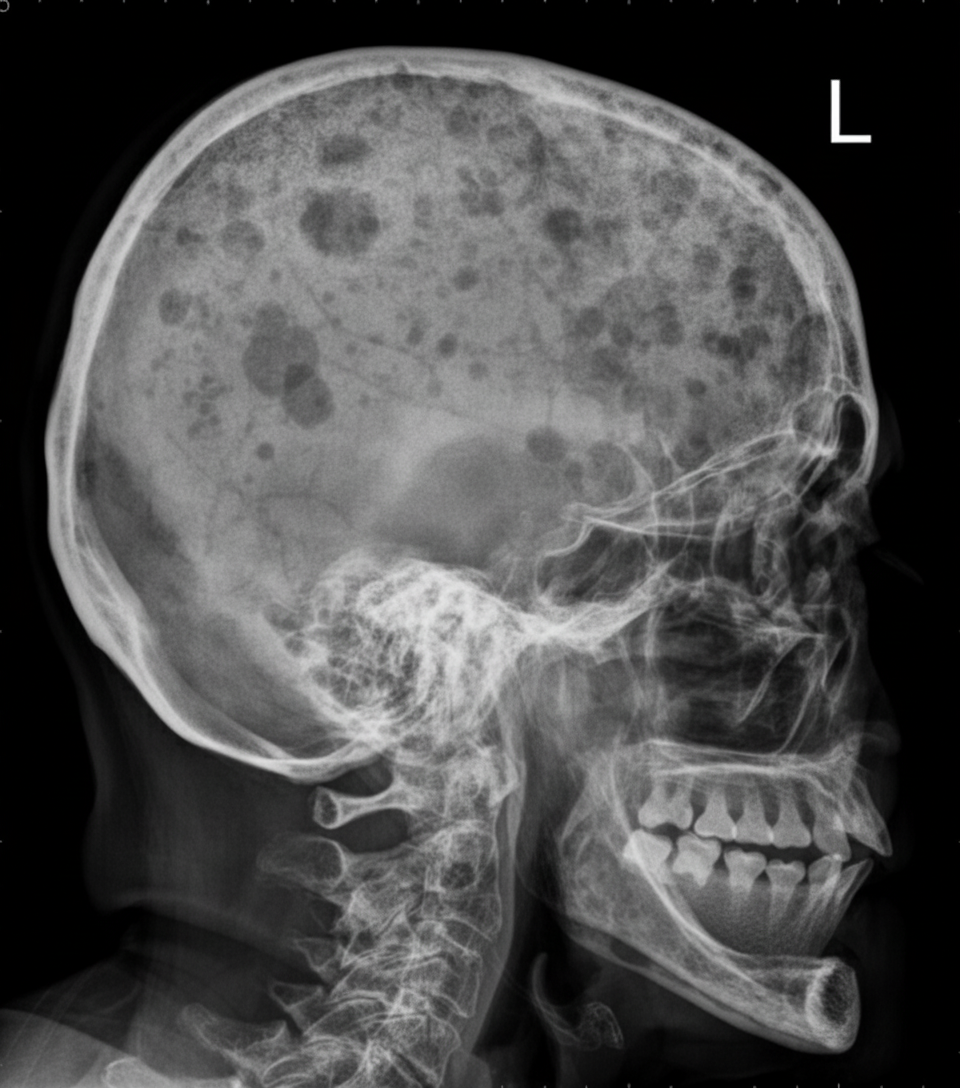

Punched out lesions in the skull are typically seen in which of the following conditions?

Which of the following conditions is characterized by the finding shown?

Explanation: ### Explanation **1. Why Multiple Myeloma is Correct:** Multiple Myeloma is a plasma cell dyscrasia characterized by the monoclonal proliferation of plasma cells in the bone marrow. These cells produce **Osteoclast Activating Factors (OAFs)**, such as IL-6 and RANK-ligand, which stimulate osteoclasts to resorb bone. On a skull radiograph, this manifests as multiple, well-circumscribed, "clean-cut" radiolucent areas without a sclerotic margin, classically described as **"Punched-out lesions."** Unlike many other bone pathologies, these lesions are typically "cold" on a Technetium-99m bone scan because there is minimal osteoblastic activity. **2. Why the Other Options are Incorrect:** * **Hyperparathyroidism:** Characterized by "Salt and Pepper" skull (mottled appearance due to trabecular resorption) and subperiosteal bone resorption, most notably on the radial aspect of the middle phalanges. * **Metastasis:** While osteolytic metastases (e.g., from lung or breast) can cause lucent lesions, they usually have ill-defined, "moth-eaten" borders rather than the sharp, punched-out margins seen in myeloma. * **Osteomalacia:** This involves defective mineralization of the osteoid. The classic radiological hallmark is **Looser’s zones** (pseudofractures), not focal lytic lesions. **3. Clinical Pearls for NEET-PG:** * **Raindrop Skull:** Another term used interchangeably with punched-out lesions in Multiple Myeloma. * **Bence-Jones Proteins:** Free light chains found in urine; they do not show up on a standard dipstick (requires sulfosalicylic acid test). * **M-Spike:** Seen on serum protein electrophoresis (usually IgG or IgA). * **CRAB Criteria:** Calcium (elevated), Renal insufficiency, Anemia, and Bone lesions (the mnemonic for symptomatic myeloma). * **Note:** In a patient over 50 with punched-out lesions and an elevated ESR, Multiple Myeloma should be the first differential.

Explanation: **Explanation:** The correct answer is **Carcinoma of the prostate**. In musculoskeletal radiology, bone lesions are broadly classified as **lytic** (bone-destroying) or **sclerotic/blastic** (bone-forming). **1. Why Carcinoma of the Prostate is correct:** Prostate cancer is the classic cause of **osteoblastic (sclerotic) metastases**. On a skull radiograph, this would appear as areas of increased radiodensity (whiter patches) rather than lytic "holes." While it can occasionally be mixed, it is the least likely among the options to present as a purely lytic lesion. **2. Analysis of Incorrect Options:** * **Multiple Myeloma:** Characterized by classic **"punched-out" lytic lesions**. These are sharply defined, circular radiolucencies without a sclerotic rim, caused by plasma cell infiltration. * **Metastasis from Bronchus:** Lung cancer (bronchogenic carcinoma) is a common source of **osteolytic metastases**. It typically causes irregular, ill-defined destruction of the bone. * **Thalassemia:** While not a malignancy, severe thalassemia causes massive erythroid hyperplasia. This expands the marrow space, leading to thinning of the outer table and a **"Hair-on-end" appearance**, which is essentially a pattern of vertical trabecular lytic changes. **Clinical Pearls for NEET-PG:** * **Mnemonic for Blastic Metastases:** **"P**rostate **B**eats **B**reast **S**lowly" (**P**rostate, **B**reast—can be mixed, **B**ladder, **S**tomach/Carcinoid). * **Mnemonic for Lytic Metastases:** **"L**ead **K**ettle" (**L**ung, **K**idney, **E**ndometrium, **T**hyroid, **T**estis). * **Key Radiographic Sign:** Multiple myeloma lesions are **cold on Bone Scan** because there is no osteoblastic activity to take up the tracer.